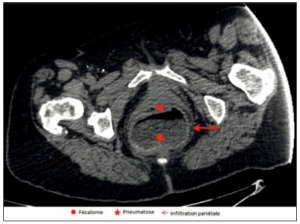

La nécrose colique

Le fécalome est une situation gériatrique fréquente, voire banale, mais dont les complications potentielles ne doivent pas être négligées. Nous présentons le cas d’une patiente décédée des suites d’une nécrose…